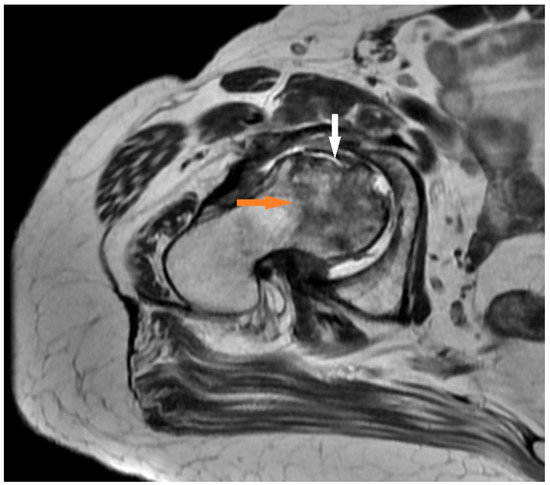

3.1.2. Case 2 (Patient No. 1)

| 1 | hip | 11 | yes | 4 | 10 | 8 | 2 |